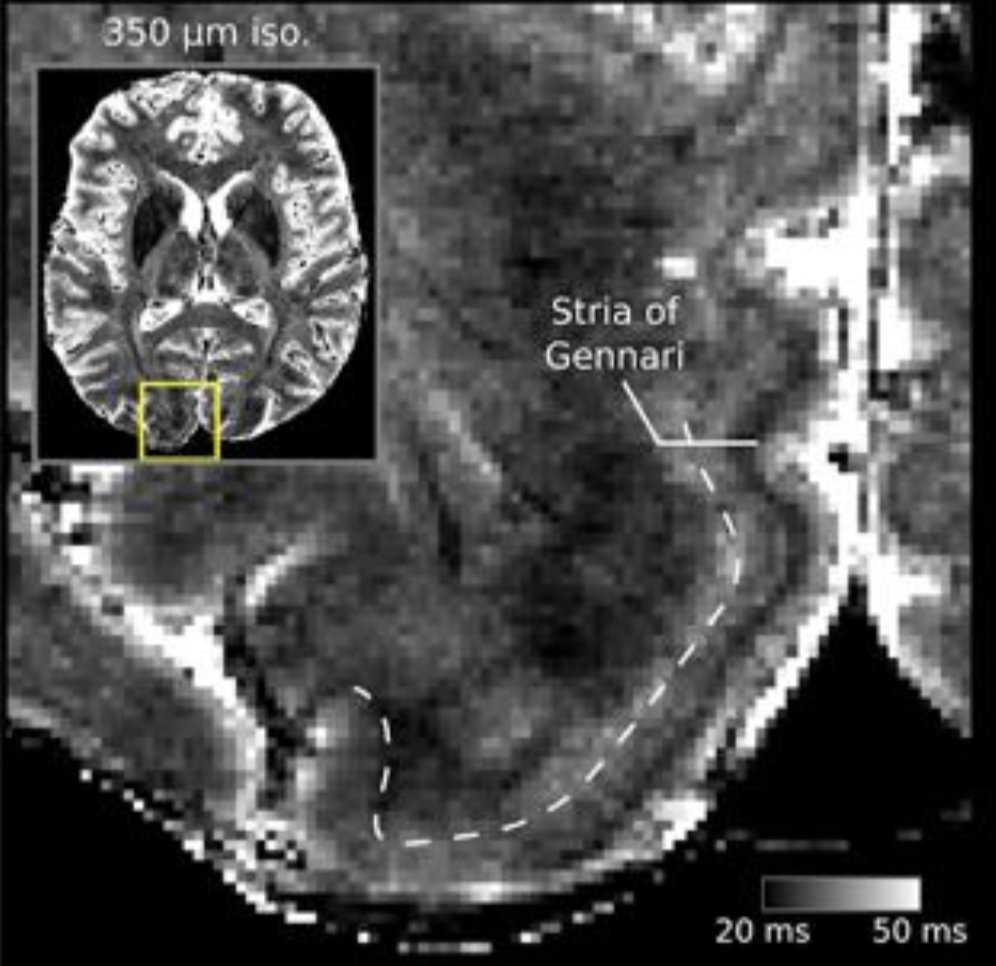

Feeling lost in the hunt for smaller voxels; No resolution will ever be high enough.

#brainartpic.twitter.com/dBEsWjBN16Thanks. Twitter will use this to make your timeline better. UndoUndo -